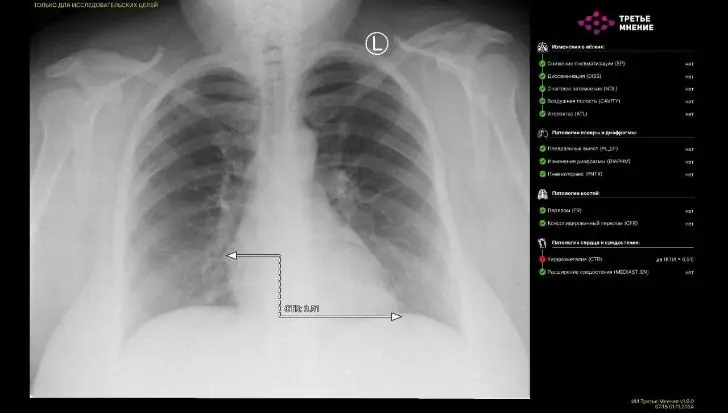

В Башкирии впервые нейросеть расшифровала рентгеновский снимок пациента. Информация об этом появилась в официальном телеграм-канале Минздрава Башкирии.

В городской больнице №21 был успешно испытан сервис «МосМедИИ»: рентгеновский снимок грудной клетки пациента был обработан цифровым помощником на базе искусственного интеллекта. В течение минуты нейросеть проанализировала изображение, выделила патологические зоны и сформировала протокол исследования.

Это — значительный шаг вперёд в цифровизации здравоохранения, позволяющий гораздо быстрее анализировать КТ, МРТ, рентгеновские и другие медицинские изображения. Однако окончательное решение поставит врач. Планируется расширение числа участвующих медучреждений и интеграция дополнительных ИИ-сервисов в рамках национального проекта «Здравоохранение».